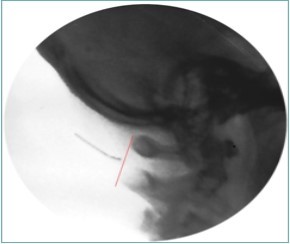

Figure 8.Lateral fluoroscopic image showing the needle in the suboccipital space; red shows the level of the spinous processes (red line). Image Courtesy of Gabor Racz, MD

Lateral fluoroscopic image showing the needle in the suboccipital space; red shows the level of the spinous processes (red line). Image Courtesy of Gabor Racz, MD